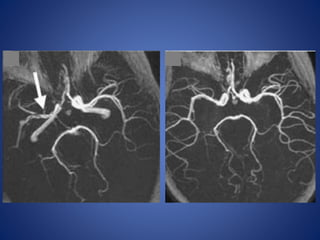

14 yr male child, K/C/O sickle cell anemia, Transcranial doppler revealed Rt. MCA

narrowing.

Courtesy : Dr M. M Shroff. Hospital for Sick Children Toronto

Follow Up

14 yr malechild, K/C/O sickle cell anemia, Transcranial doppler revealed Rt. MCA narrowing. Courtesy : Dr M. M Shroff. Hospital for Sick Children Toronto